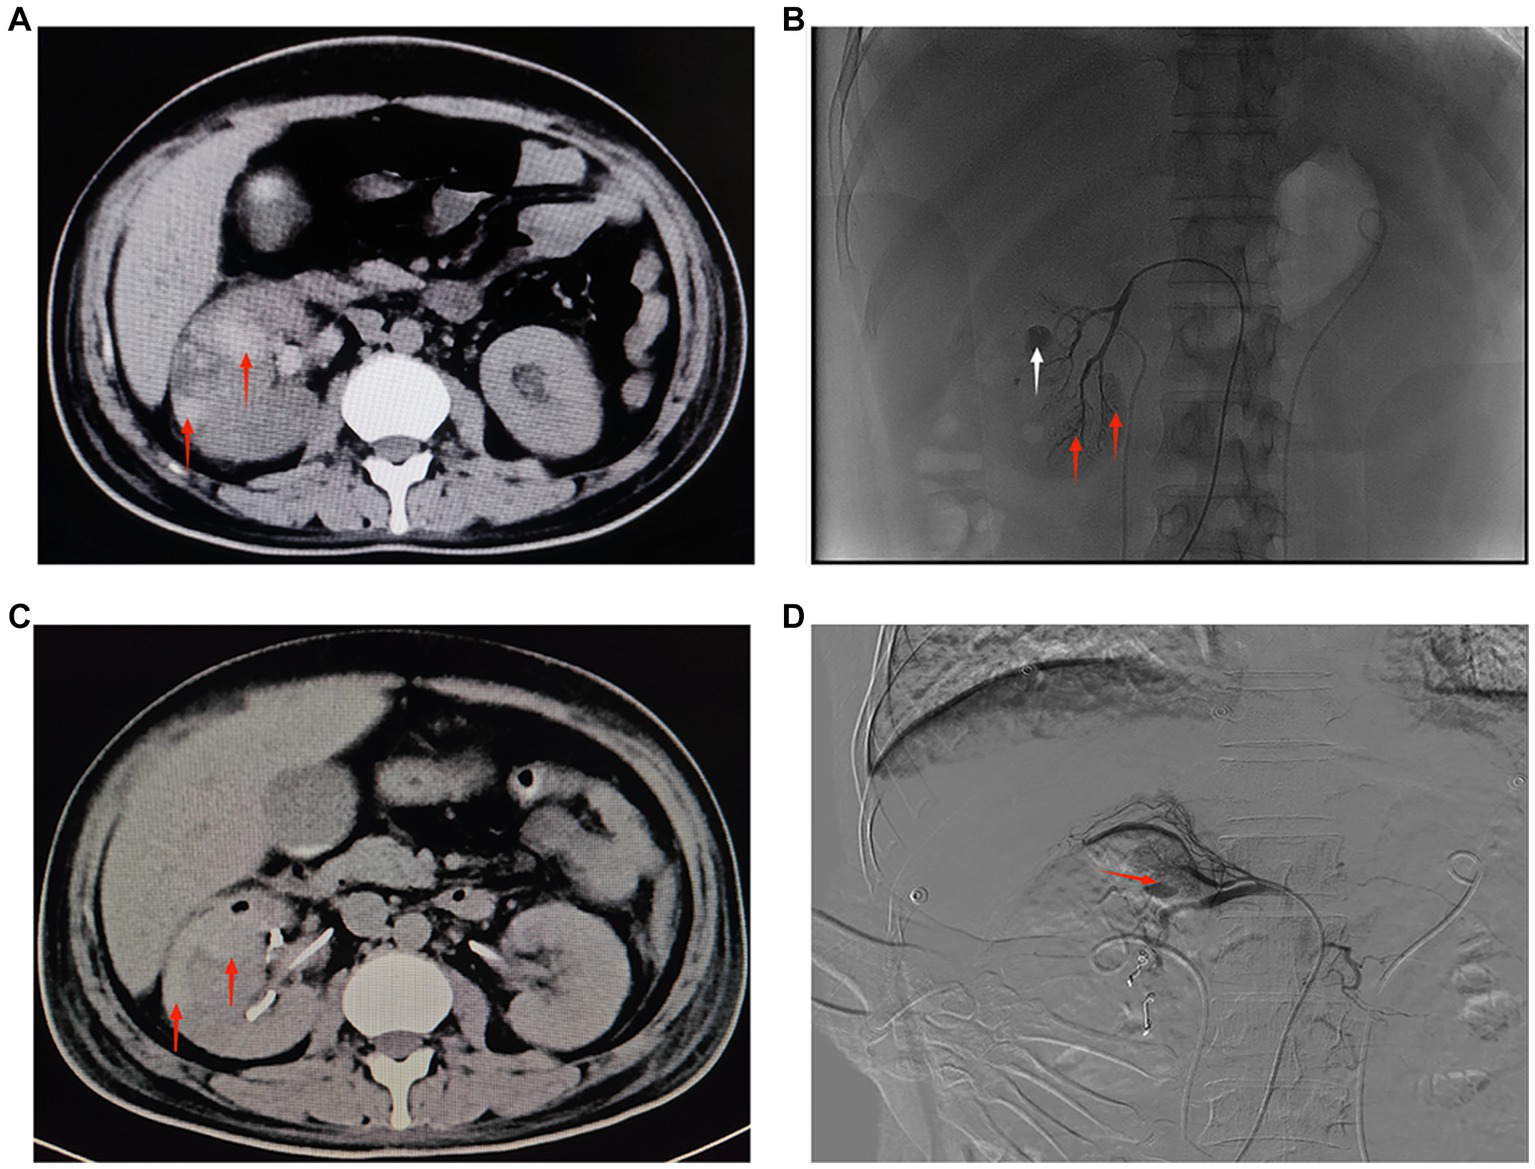

Figure 2

(A) CT of both kidneys. The right kidney is increased in size, heterogeneous in density, with multiple flaky hyperdense shadows, and clear perirenal space in both kidneys. The red arrow shows a hematoma in the lower pole of the right kidney (September 19, 2022, day 16 of admission). (B) Angiography of the right renal artery. Red arrows show active extravasation of multiple subsegmental arteries supplying the lower pole. White arrow indicates pseudoaneurysm formation (September 19, 2022, day 16 of admission). (C) CT of both kidneys. The right kidney is increased in size, heterogeneous in density, with multiple patchy hyperdense shadows, and clear perirenal space in both kidneys. The red arrow shows a hematoma in the upper pole of the right kidney (September 22, 2022, day 19 of admission). (D) Digital subtraction angiography of the right renal artery. Red arrow indicates active extravasation of the subsegmental artery supplying the superior pole (September 22, 2022, day 19 of admission).